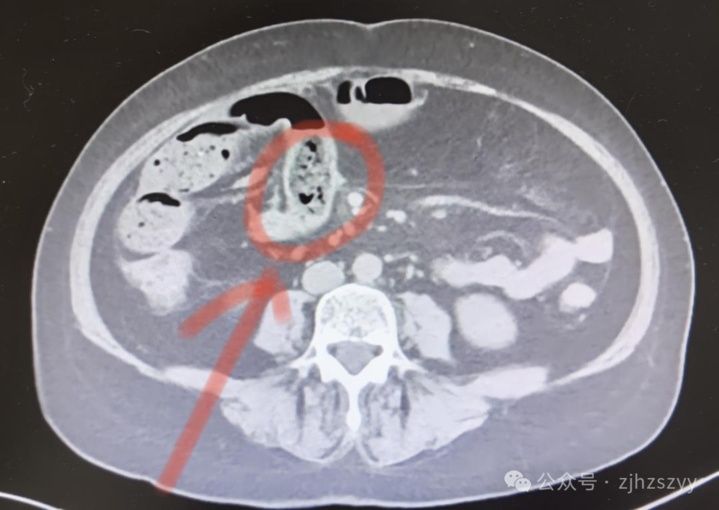

10月21日,浙江杭州58岁的宋女士一连吃了好几个柿子。没想到第二天,腹部就出现阵阵绞痛,难以忍受,到杭州市中医院检查确诊为 小肠肠梗阻。在收治入院过程中,她的病情急转直下,还出现了腹腔积液。医院紧急安排手术,将一块 比鸡蛋还大、坚硬如石的“柿石”取出,一周后患者顺利康复。

这是因为柿子中含有较多的鞣酸和果胶,在胃酸的作用下, 鞣酸可与蛋白质结合,形成分子较大且不溶于水的鞣酸蛋白,再与其他食物残渣凝结成块,越积越大就会形成“柿石”。

➤“柿石”在胃内不断摩擦,可能使人出现腹胀、胃痛、恶心、呕吐等症状。

➤ 如果“柿石”进入肠道又无法顺利排出,则可能导致肠梗阻,严重者会引发肠坏死,甚至引起弥漫性腹膜炎而危及生命。